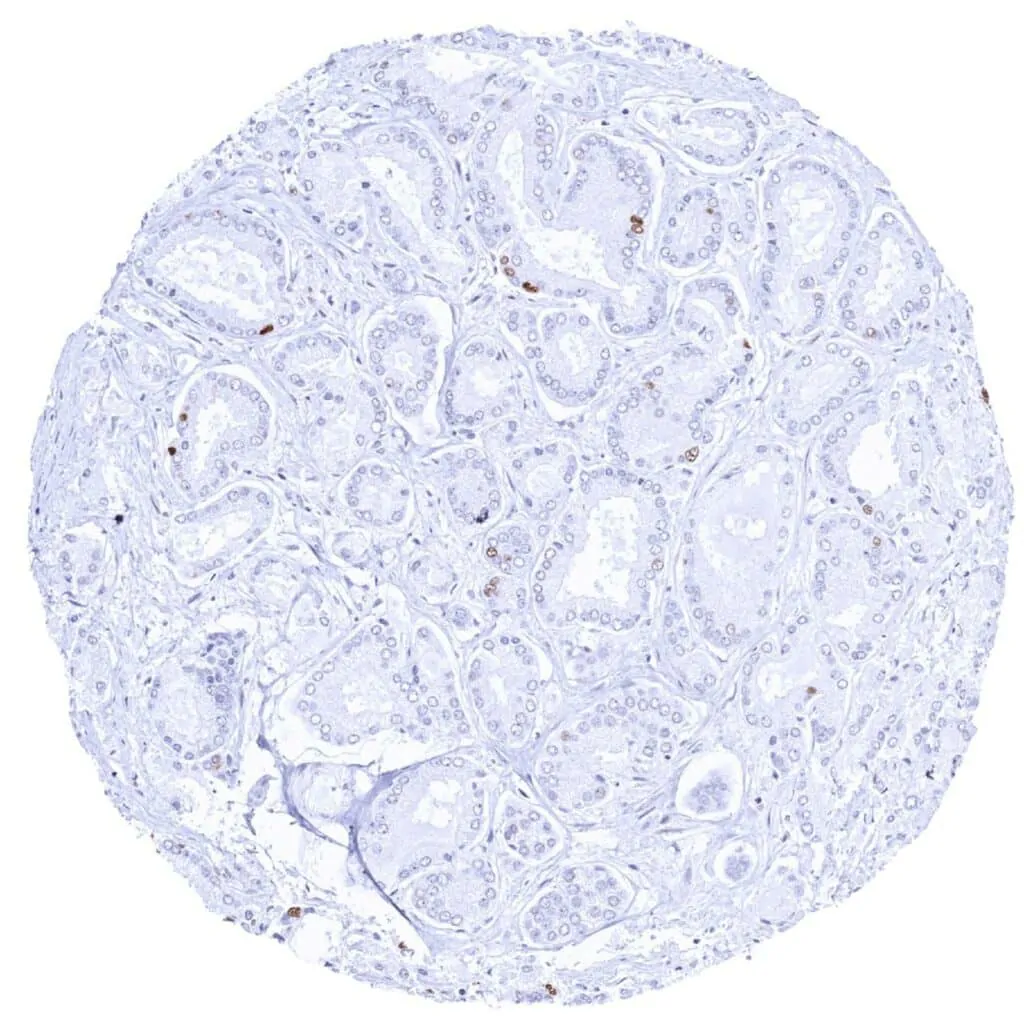

Thyroid – Follicular adenoma with variable MCM2 staining of a fraction of tumor cells